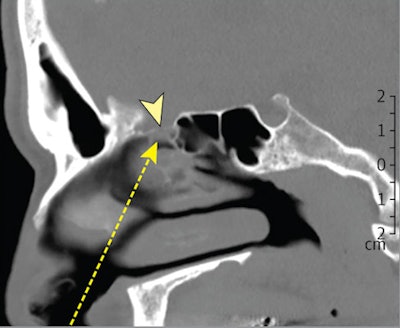

The patient underwent a nasal endoscopy nine months after the onset of his initial symptoms. During the exam, a clear nasal secretion was noticeable between the middle turbinate and the septum on the right side. A CT scan showed a defect in the lamina cribrosa on the right side. A previous brain CT scan from 2011 showed no skull base defect or other pathology.

CT scan of a defect in the lamina cribrosa. Image courtesy of JAMA Network.An analysis of the patient's nasal discharge showed a high level of the beta-trace protein (23.7 mg/L) in the nasal secretion (normal range < 6 mg/L). The beta-trace protein test is a quick, noninvasive, and inexpensive method to detect CSF fluid in nasal secretions.